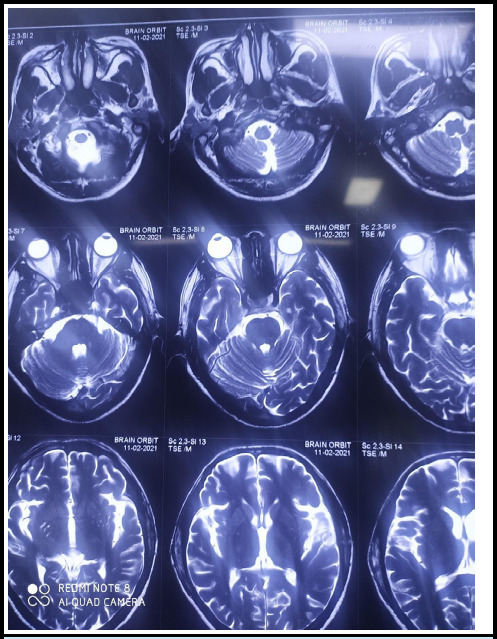

Abstract: Visual loss following a spine surgery in a prone position is a disastrous and irreversible complication. Moreover, the recommended treatment for such visual loss is lacking and the outcome is not so satisfactory. A 38-year-old gentleman developed profound right sided visual loss after an uneventful cervical spine surgery in a prone position that lasted approximately two and half hours. Immediate ophthalmic consultation was done and the case was diagnosed as right-sided central retinal artery occlusion. Despite the initiation of vasodilatation, anticoagulation, and adequate fluid infusion, satisfactory improvement was not achieved. Extensive review of pertinent literature highlighted limited efficacy of treatments for postoperative visual loss after prone spinal surgery, further emphasizing the importance of preventive measures as the cornerstone in such procedures.

Abstract Image